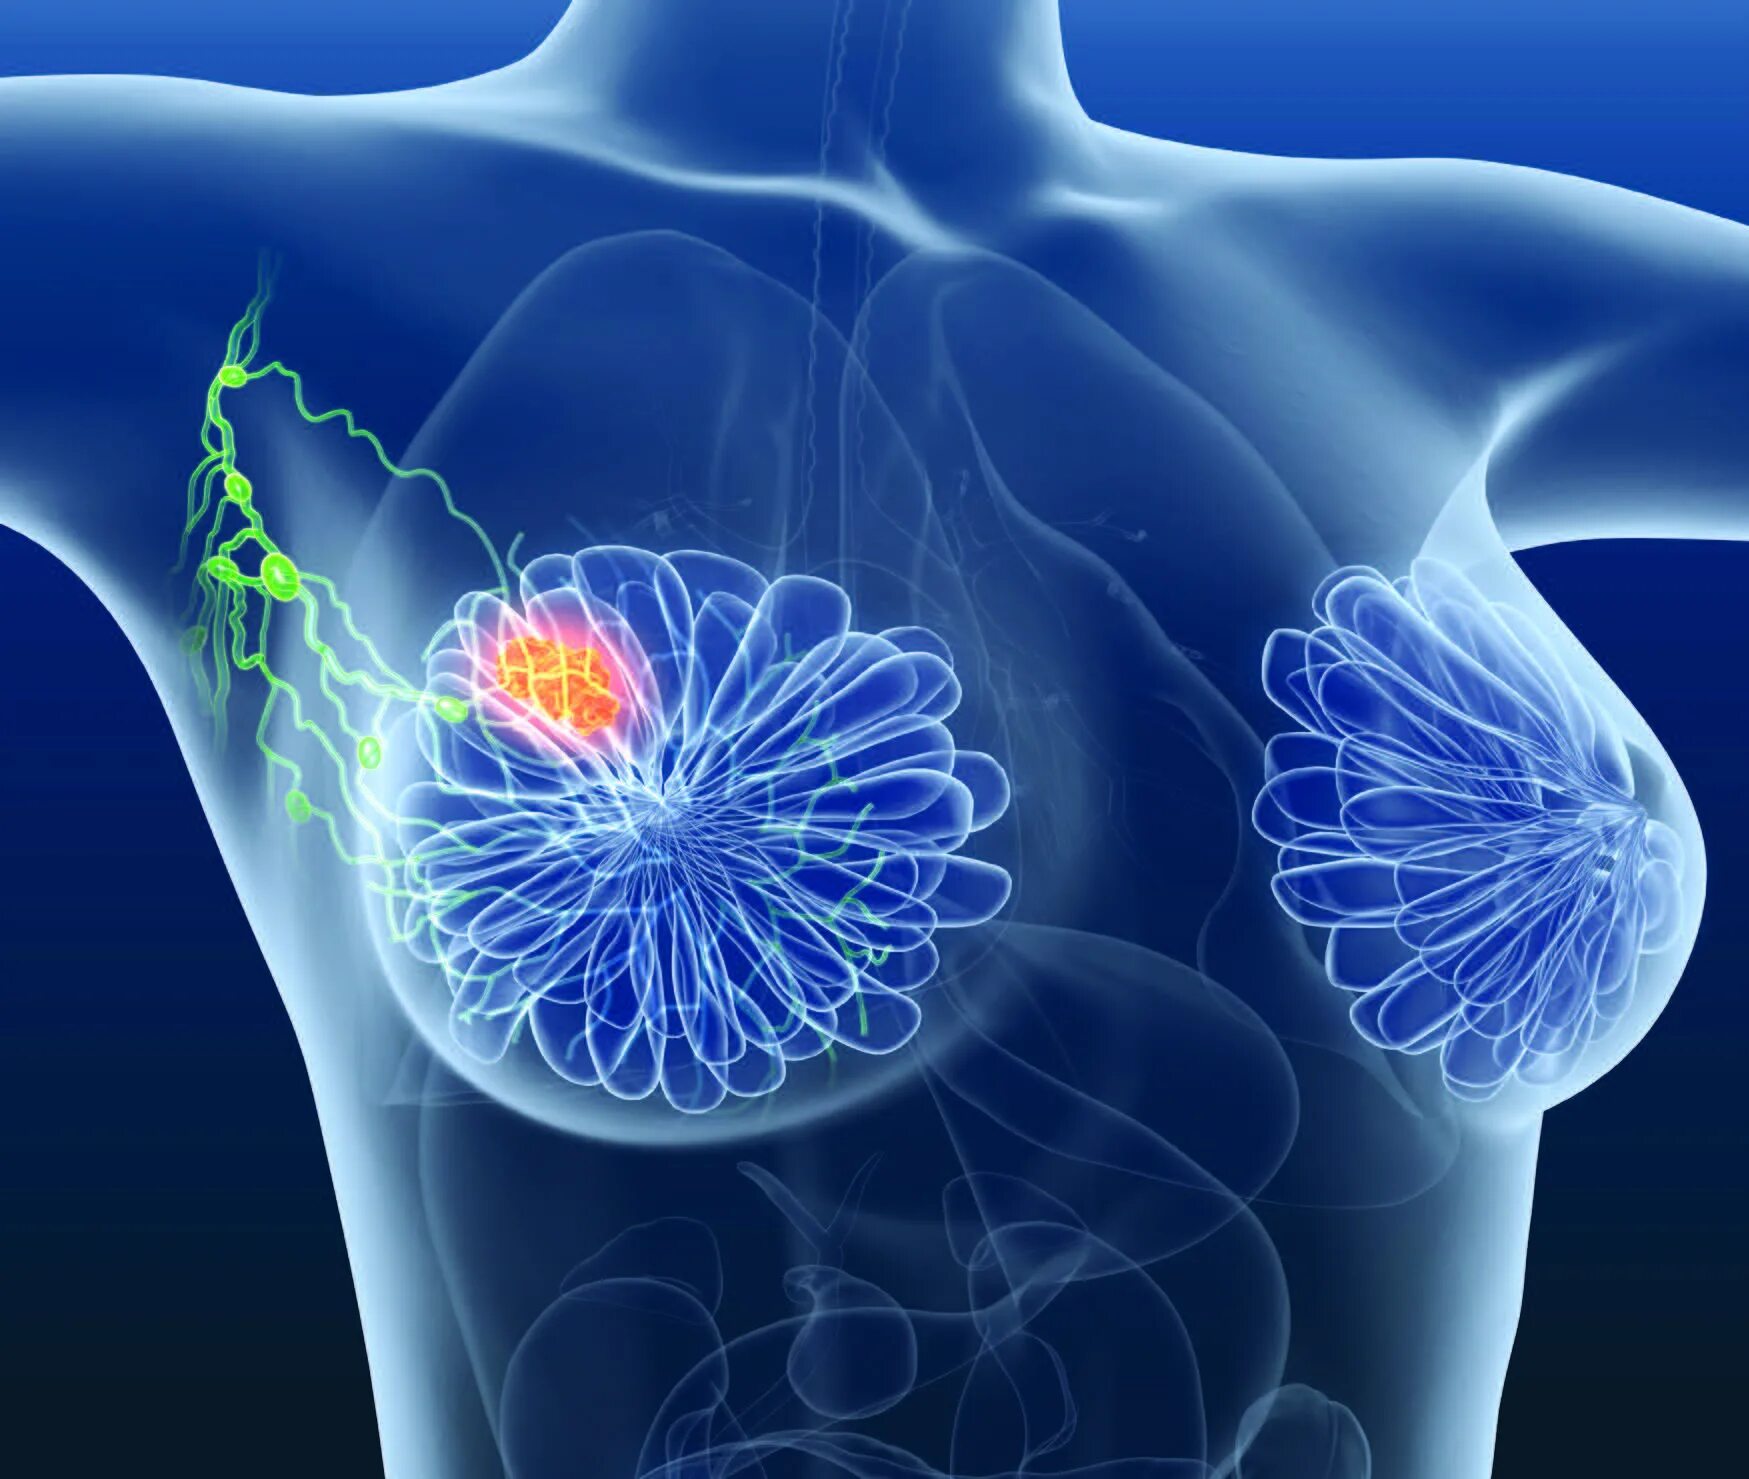

Опухолевидное образование молочной железы